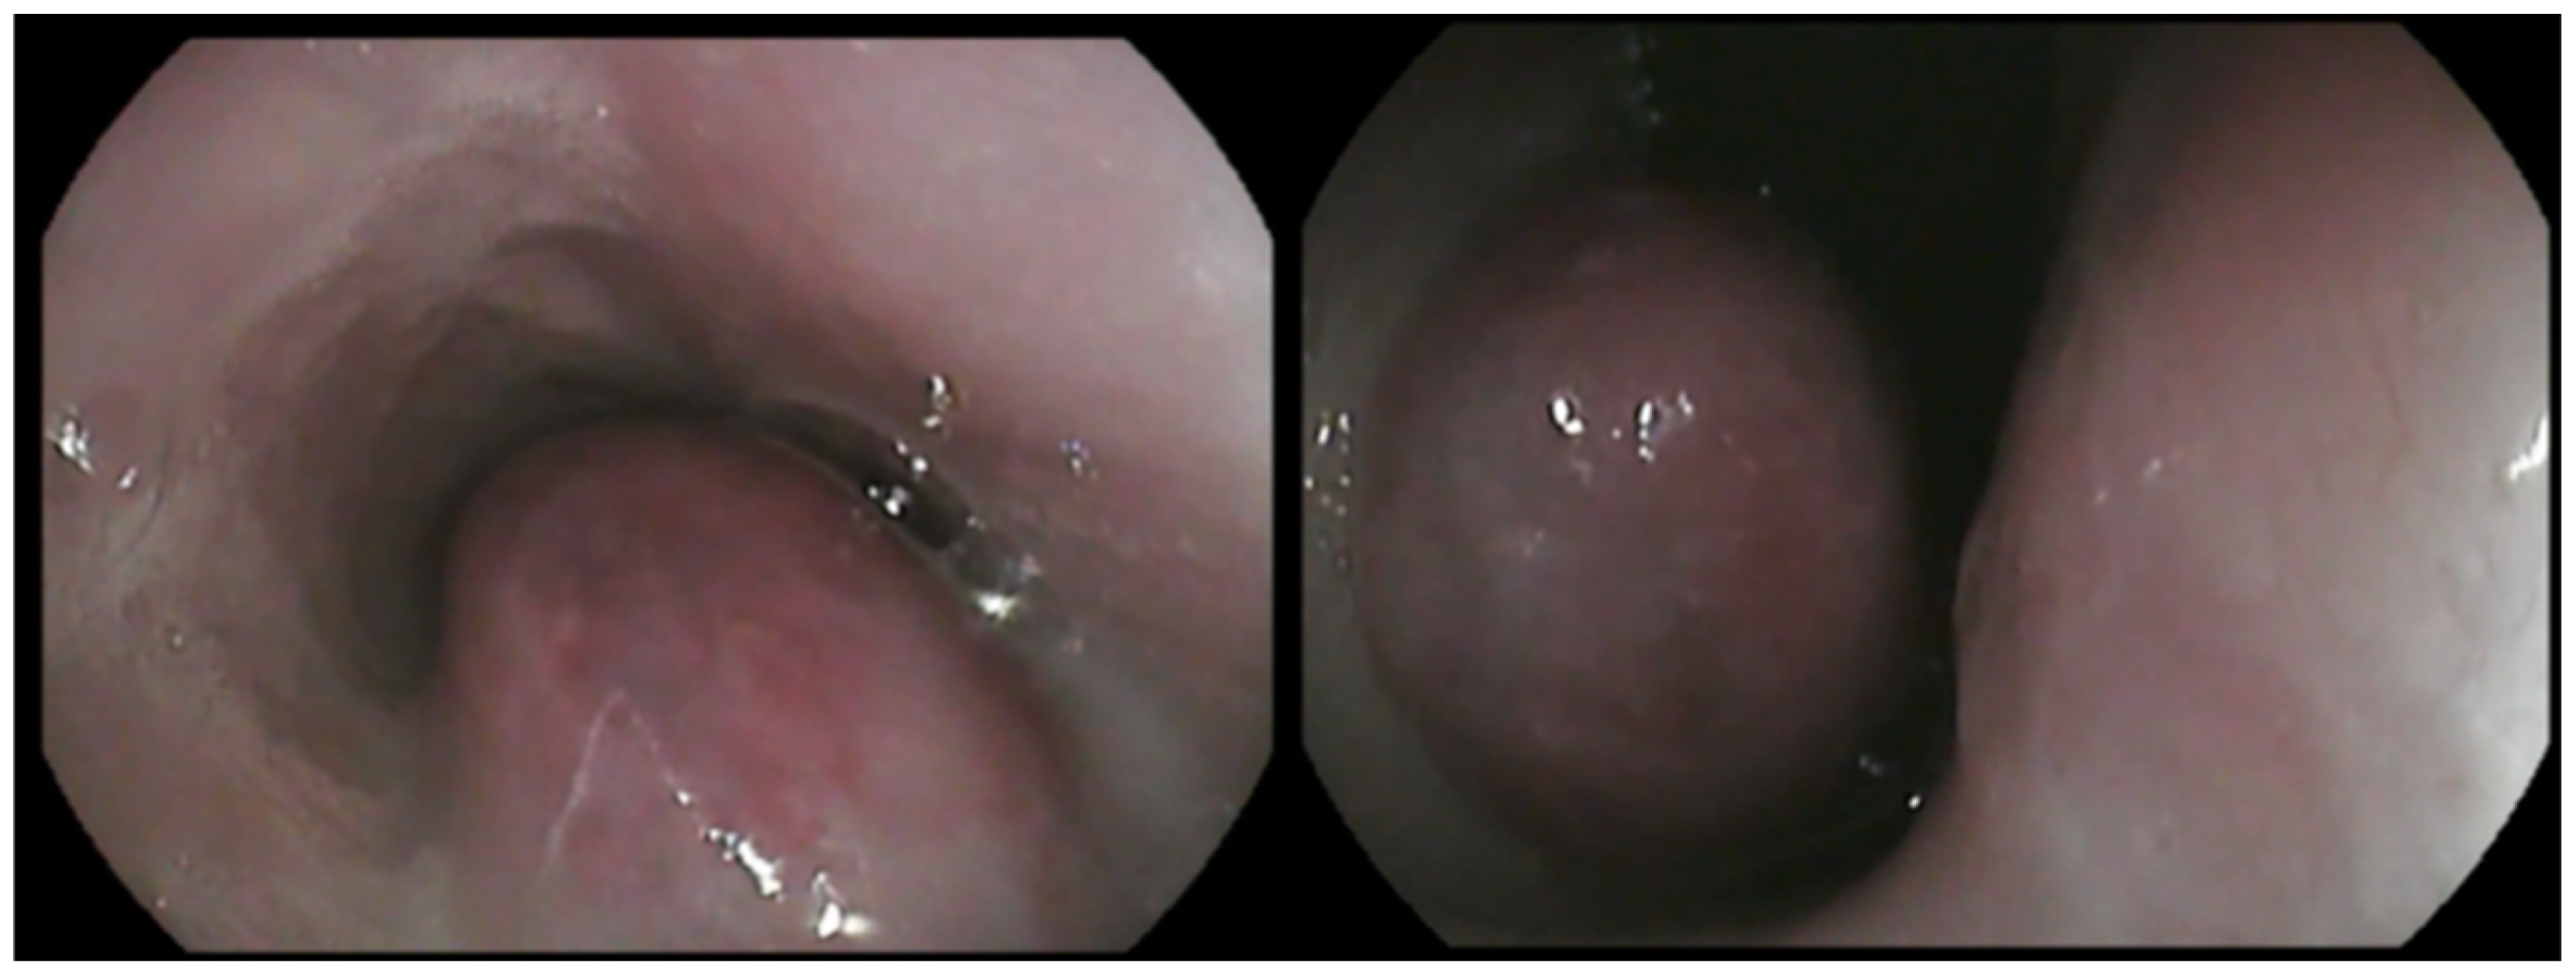

A large, highly vascular, obstructive, solitary mass with a smooth surface was detected (Figure 2). Endoscopic biopsies of the mass were collected for histopathologic examination. Specifically, seven biopsy samples from stomach, eight from duodenum, and eight from the esophageal mass were obtained using a 2.2 mm biopsy forceps. Biopsy samples were placed in 10% neutral buffered formalin and embedded in paraffin until histopathologic examination. The owner was instructed to feed the dog a high-energy, moist, home-made diet fed from an upright position to facilitate esophageal transit until histopathologic results were available.

Figure 2.

Macroscopic view of the esophageal lumen during the esophagoscopy. A large, highly vascular, obstructive, solitary mass with a smooth surface was noted. The mass was located between 1st and 7th thoracic vertebra.

Follow-up esophagoscopies were performed every 3–6 months after surgical excision and did not show evidence of tumor regrowth in the esophagus until 18 months after surgery, when recurrence of the mass was identified (Figure 10). The dog still remains asymptomatic, with the exception of one episode of vomiting and regurgitation, which was resolved after symptomatic treatment.

Figure 10.

Macroscopic view of the esophageal lumen during follow-up esophagoscopy. Notice a regrowth of the mass (18 months after the surgical excision).